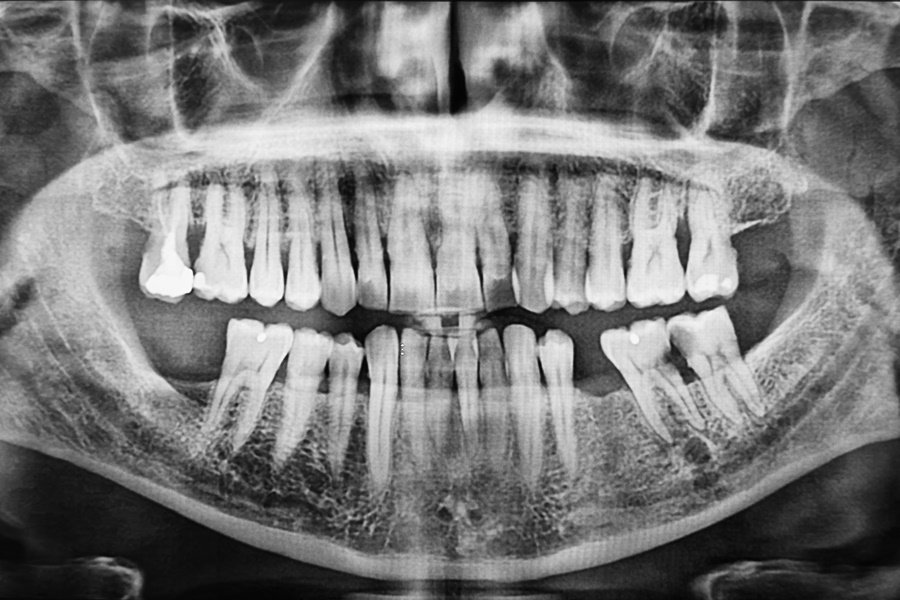

Radiografía panorámica de un paciente con varias ausencias dentales, muestra qué ocurre cuando no se reemplazan las piezas dentales perdidas.

Desplazamientos dentales y alteraciones en la oclusión

Cuando un diente se pierde y no se reemplaza, los dientes vecinos tienden a desplazarse hacia el espacio vacío. Este movimiento, conocido como migración dentaria, puede generar problemas oclusales importantes.

Entre las consecuencias más habituales se encuentran:

• Inclinación o rotación de las piezas adyacentes.

• Erupción excesiva de los dientes antagonistas.

• Aparición de contactos prematuros o interferencias oclusales.

Estas alteraciones provocan desequilibrios que afectan tanto a la función como a la estabilidad de la boca, y pueden generar dolor mandibular o disfunciones en la articulación temporomandibular (ATM).

Reabsorción ósea en la zona edéntula

El hueso alveolar necesita la estimulación mecánica que proporciona la raíz dental para mantenerse en buenas condiciones. Cuando se pierde un diente, el hueso de esa zona deja de recibir dicha estimulación y comienza a reabsorberse de forma progresiva.

Esta pérdida de volumen óseo tiene efectos a medio y largo plazo:

• Dificulta la colocación de implantes dentales en el futuro.

• Modifica el contorno facial, provocando un aspecto más envejecido.

• Reduce la estabilidad de prótesis removibles si no se adaptan correctamente.

Cuanto mayor es el tiempo sin reemplazo, mayor es la reabsorción ósea y más complejos pueden ser los tratamientos rehabilitadores necesarios.